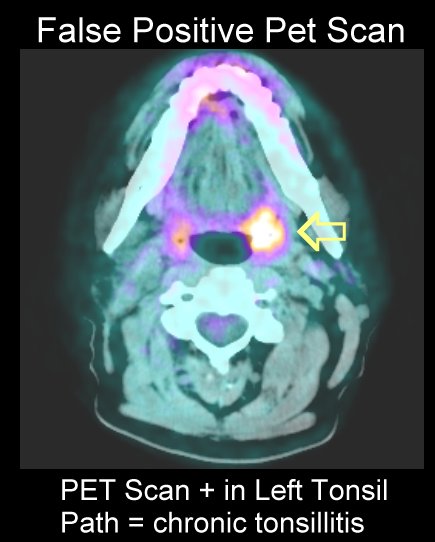

- Tonsil PET

scans:

here,

tonsil nodes,

here ,

here